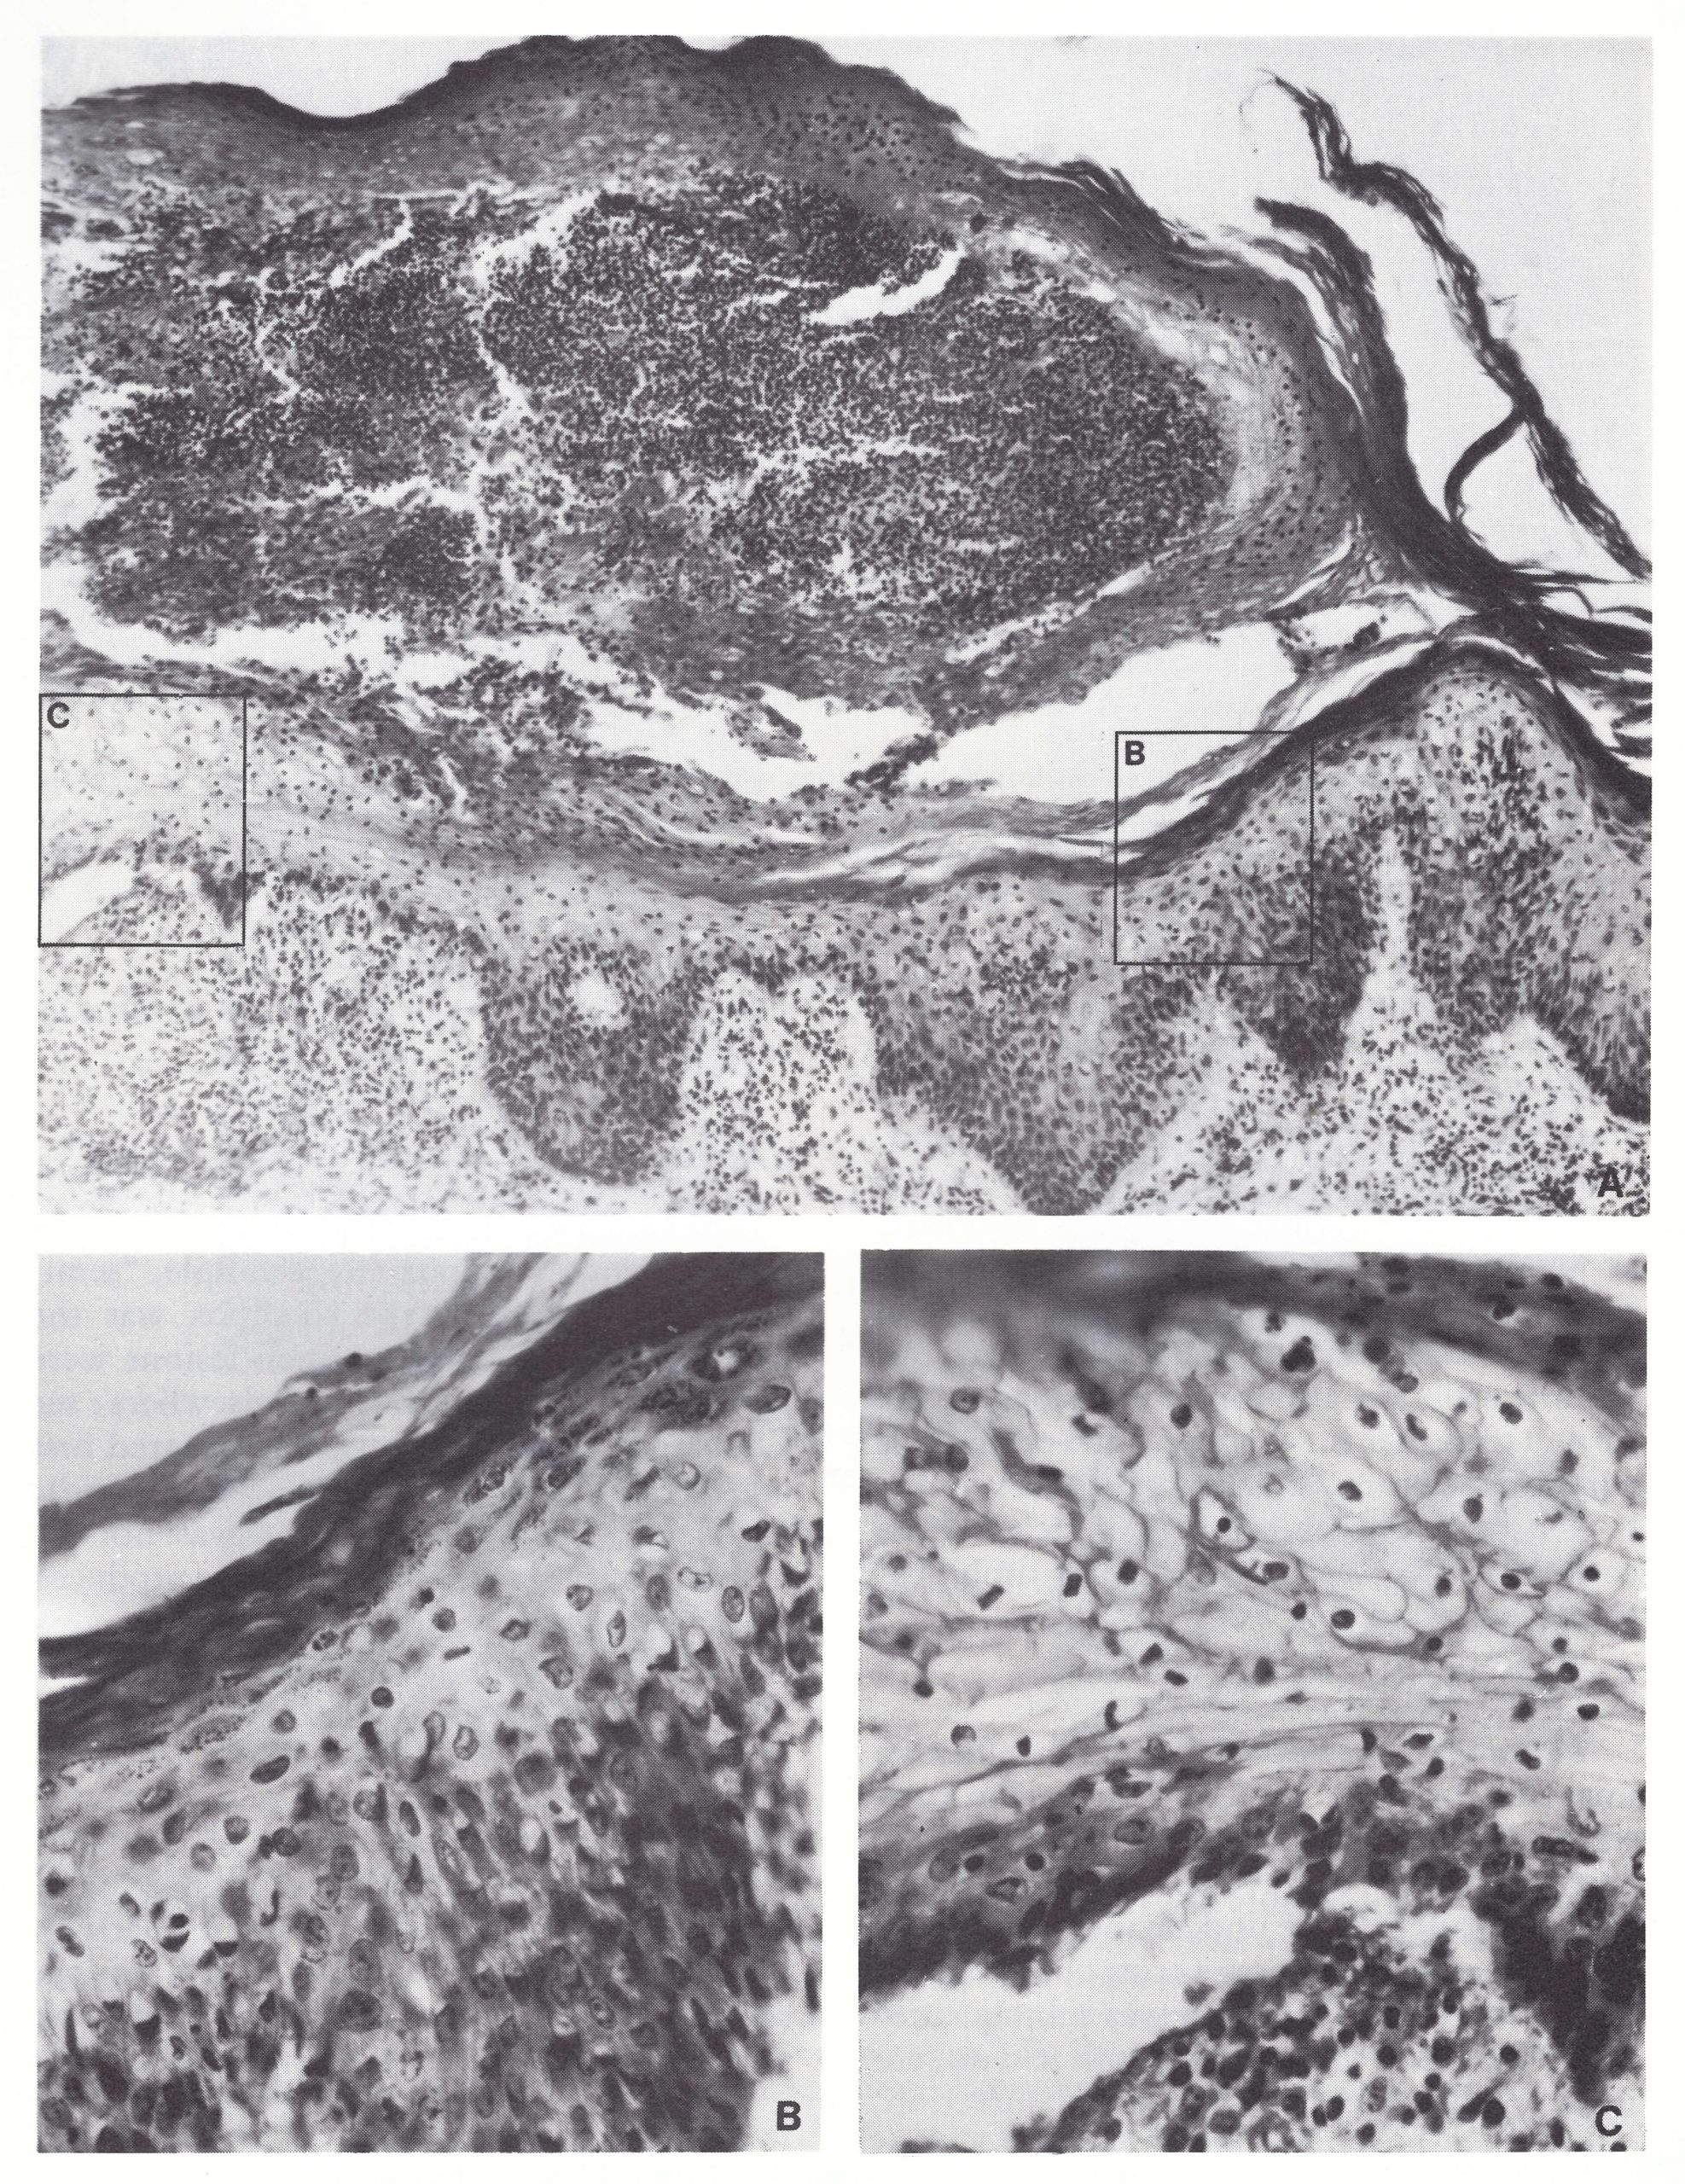

Plate 3.3. Stages in the development and evolution of the skin lesion. A: The earliest change was oedema of the dermis leading to the separation of epithelial cells of the papillae and lymphocytic infiltration in the dermis, especially around the small vessels. Ballooning degeneration was seen in a few cells in the lower Malpighian layer. B: These changes progressed and the small vessels became dilated and engorged. Inclusion bodies were also visible adjacent to cells showing ballooning degeneration. In early haemorrhagic-type smallpox, illustrated here, there was pronounced haemorrhaging into the dermis. C: As the pathological process progressed, the epithelial cells broke down by reticulating degeneration to produce a multilocular vesicle. D: The vesicle formed by coalescence of the smaller cavities became infiltrated with polymorphonuclear leukocytes to produce a pustule, around which were cells containing inclusion bodies. E: The fully developed pustule became packed with polymorphonuclear leukocytes and the epithelium on either side of the pustule proliferated. F: Eventually the pustule became a crust, beneath which new epithelium grew in to repair the surface. Such lesions, in which the sebaceous glands were not involved, healed without leaving a pockmark. (From Michelson & Ikeda, 1927.)

Plate 3.4. Fully developed vesicle. A: Loculated cavities with relatively acellular exudate formed as a result of reticulating degeneration of the middle layers of the epidermis. Unaffected keratohyalin and horny layer form the roof of the vesicle; at its base, cells are undergoing hyaline fibrinoid degeneration, which is best seen in B. the higher power view. Haematoxylin and eosin. A x 130; B x260. (From Bras, I952a.)